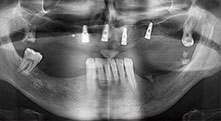

Pr Bratu : Nous avons volontiers recours à la technique sandwich pour les augmentations mandibulaires latérales. La préparation d'un couvercle osseux est réalisée à l'aide de la scie piézoélectrique et le fragment crestal est fixé à l'aide de microvis. Nous plaçons un mélange de matériau de substitution osseuse autologue et xénogénique entre les deux. Cela fonctionne très bien. Il faut toujours s'assurer que les coupes verticales aient des dimensions suffisantes lors du clivage de la crête alvéolaire dans la mandibule. Sinon, l'os risque de se casser facilement.

Pr Bratu : J'estime que la chirurgie piézoélectrique a fait faire un grand bon en avant à la chirurgie orale. Grâce à cette technique, la préparation osseuse est plus sûre et plus facile. Par exemple, les extractions entraînent une perte osseuse minime. C'est très important d'un point de vue esthétique, surtout si la pose d'implants est prévue immédiatement.

La chirurgie piézo est également plus sûre pour les tissus mous. Ainsi, les dommages causés aux membranes dans le sinus ont pratiquement disparu, de même que les atteintes nerveuses lors du prélèvement des blocs osseux. On dispose également de données indiquant une diminution des gonflements et des douleurs postopératoires. La chirurgie piézoélectrique convient idéalement à la préparation des septa sinusiens. Et dernier avantage, mais pas le moindre, nos patients apprécient le caractère atraumatique de cette technologie.